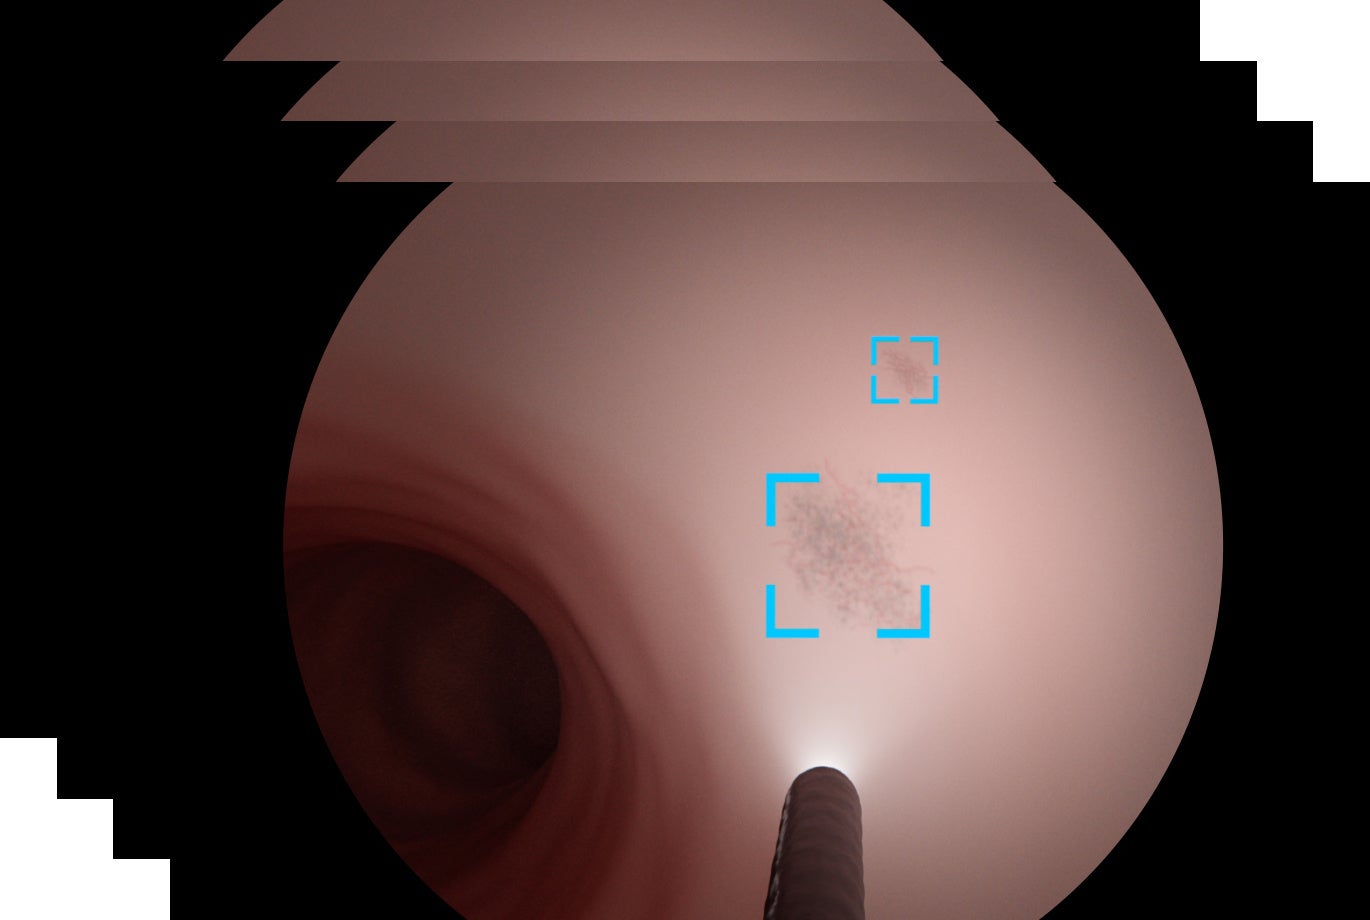

富士フイルムが開発した内視鏡AI診断支援技術は、胃・食道・大腸の内視鏡検査中にリアルタイムに画像を解析。医師がモニターで見ている内視鏡映像上で、がんの疑いがある領域を検出し、枠で囲って表示することで、医師の診断を支えます。